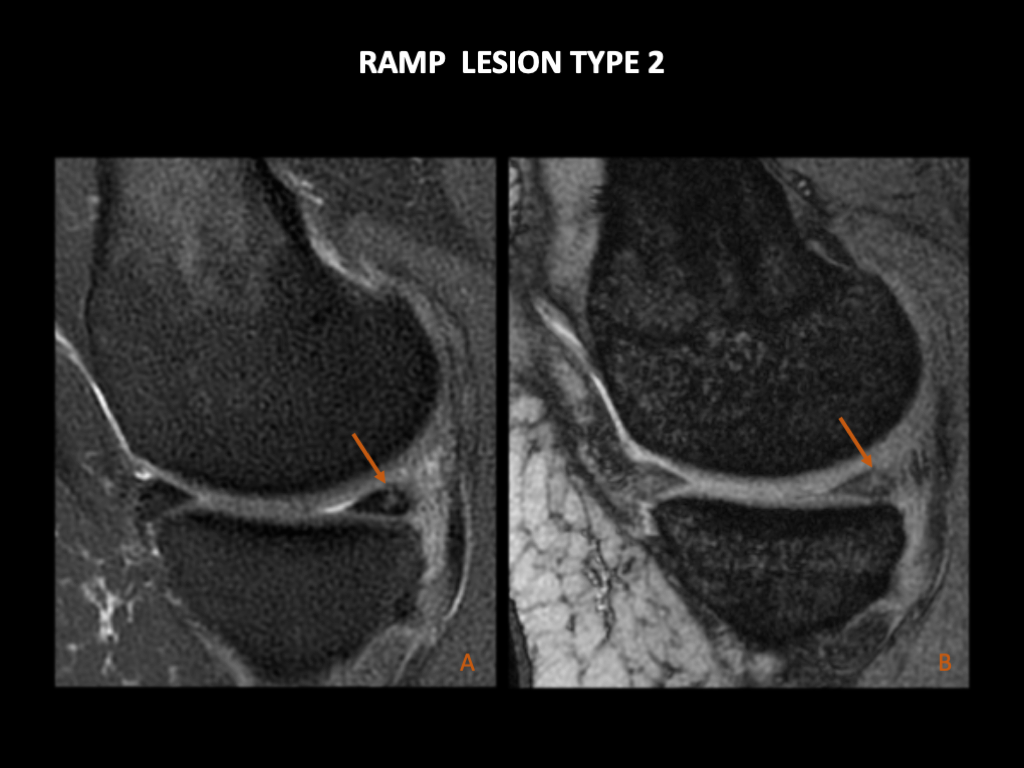

图 15:女,37岁,左膝疼痛2个月。矢状位PD FS和矢状位GRE。内侧半月板后角有一条垂直的液体信号线(箭),达到上关节面,但没有达到胫骨方面的半月板。这是一个部分的纵向垂直撕裂。半月板关节囊和半月板胫骨韧带没有受到影响。这与Greif和Thaunat Ramp2损伤一致。